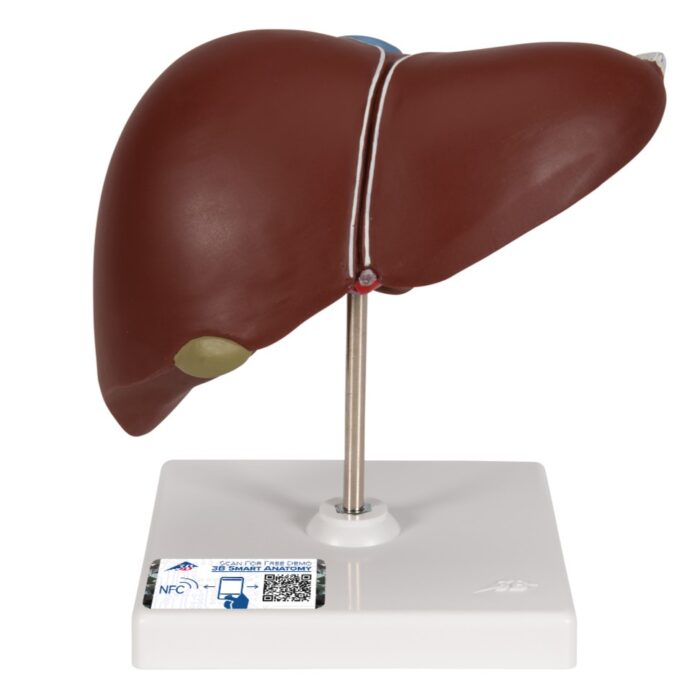

UK 3B Liver with gall bladder

Teaching Aids – Liver with gall bladder

UK 3B Liver with gall bladder

This realistic model shows the anatomy of the liver and gall bladder. The Liver with gall bladder shows:

This high quality liver with gallbladder replica is delivered on removable stand.

- Realistic UK 3B Liver with gall bladder

- Supplied on removable stand

- Size: 18x18x12cm